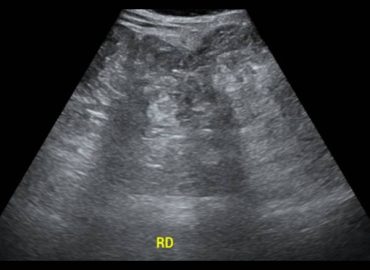

Niño de 3 años, sin antecedentes previos. Motivo de consulta: fiebre y disuria de 5 días de evolución Ecografía renovesical […]